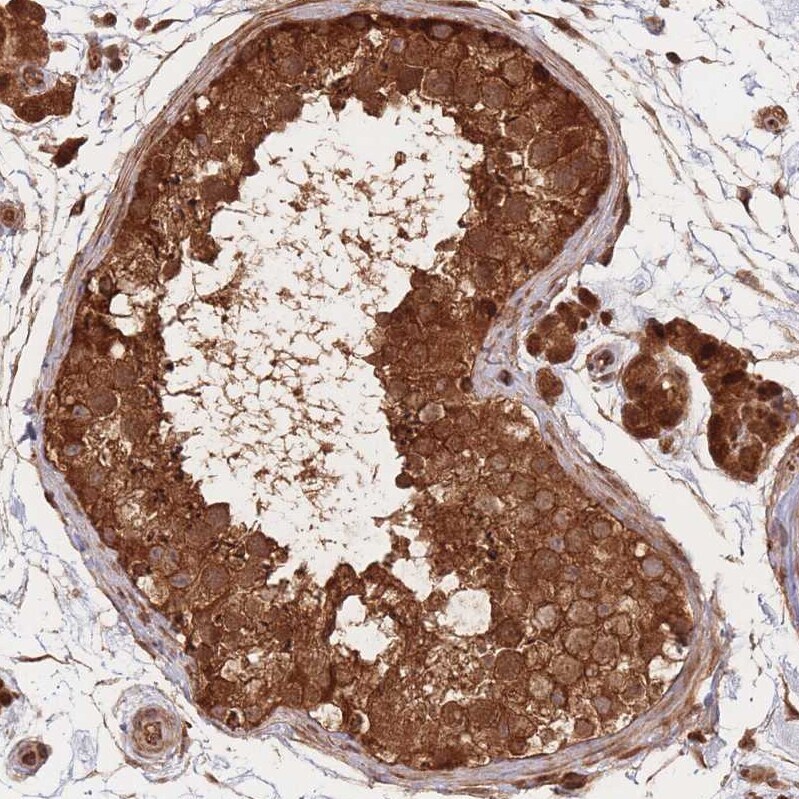

Supportive validation

- Submitted by

- Invitrogen Antibodies (provider)

- Main image

- Experimental details

- Immunohistochemical analysis of PODXL2 in human pancreas using PODXL2 Polyclonal Antibody (Product # PA5-83597) shows strong cytoplasmic and nuclear positivity in exocrine glandular cells.